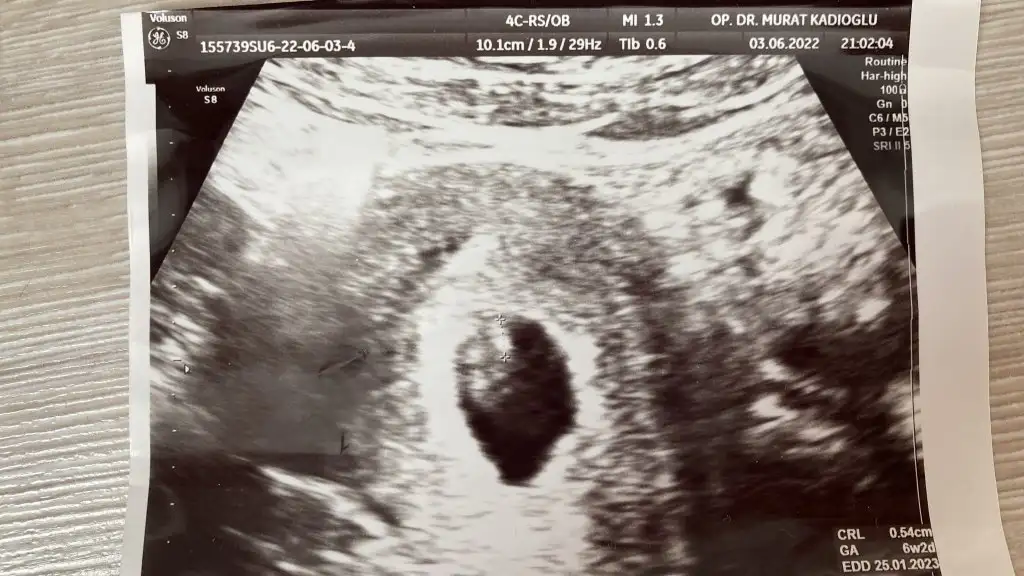

selam canım 7 ve haftalık karından ultrason görüntümü paylaşıyorum tahminin nedir acaba

Eklentiler

• 7. hafta.webp

7. hafta.webp

48,3 KB · Görüntüleme: 48